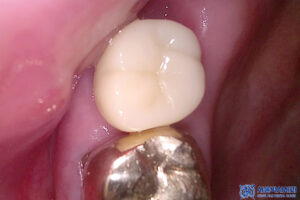

이후 먼저 왼쪽 위 임플란트 먼저

보철 작업을 시작하였습니다.

맞춤형 지대주를 제작 후

그에 맞는 최종보철을 제작하여

맞춰본 뒤 영구접착을 하였습니다.

왼쪽 위가 마무리 된 후

마무리 후 사진입니다.

그리고 어금니 쪽에 이전에 진행했던

보철보다 훨씬 마음에 드신다며

크라운과 임플란트 보철 모두

심미적으로 자연스럽고

꼭 맞게 잘 설계되었다며

매우 좋아해주셨습니다.